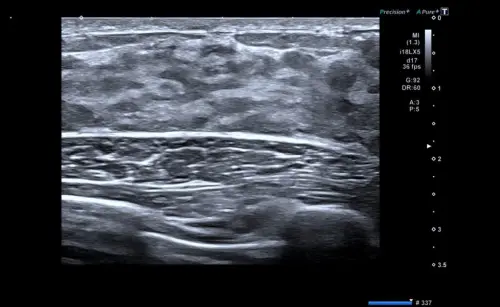

Пример УЗИ молочной железы. Демонстрация процесса сканирования в реальном времени.